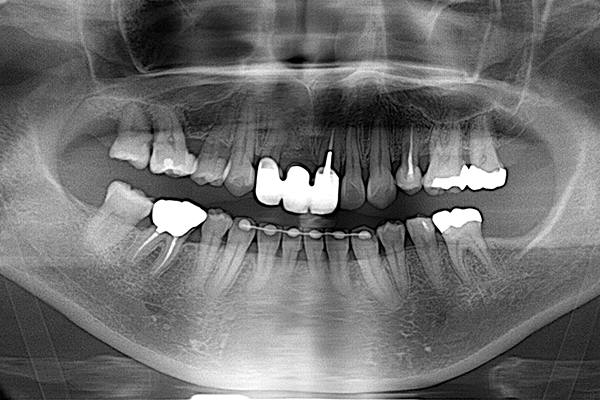

主訴は「全ての歯を綺麗に治したい」とのことで来院されました。診断の結果、複合的な問題が見つかり、歯周病治療、矯正治療等複数の治療を約3年ほど順番に進めていきました。最終的には歯の色味も回復させることができ、患者さんにも満足していただけました。

| 患者 | 45歳 女性 |

|---|---|

| 主訴 | 前歯が取れた。 |

| 診断 | このケースはかなりひどい叢生があり、矯正治療が必須であると説明。 |

| 治療内容 | 左上5は保存不可能のため、右上より5を左上に移植 矯正終了後補綴治療 |

| 治療期間 | 約3年半 |

| 費用 | 200万円 |